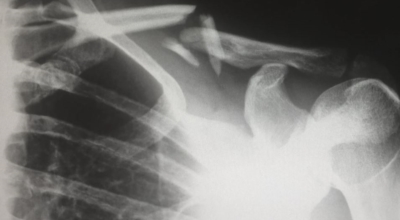

중년에 접어들면 뼈에 좋은 칼슘제과 관절영양제를 찾게 됩니다. 영양제도 좋지만 뼈와 관절에 좋은 운동과 식이요법도 중요해요. 뼈에 이상이 생기면 골다공증으로 이어지므로 특히나 관리를 잘 해야 해요. 일반적인 때에 음식을 통해 어떻게 관리를 하면 되는지 골다공증에 좋은 음식을 알려드리려고 해요.